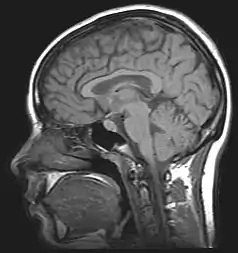

L'apotemnophilie est un trouble neurologique dans lequel un individu exprime un fort désir spécifique de subir l'amputation d'un ou plusieurs membres du corps en bon état[1],[2]. Cela pourrait être dû à une lésion du lobe pariétal droit, ce trouble ayant des caractéristiques communes avec la somatoparaphrénie[2]. Lors d'une très forte expérience, certains individus atteints d'apotemnophilie ont tendance à se sentir mécontents de leurs corps et veulent à tout moment retirer un membre en bon état, une condition nommée trouble identitaire relatif à l'intégrité corporelle. Certains apotemnophiles recherchent l'aide de chirurgiens pour une amputation ou se blessent volontairement un membre pour forcer une amputation médicale urgente[3]. Une définition à part, bien qu'occasionnellement morbide, de l'apotemnophilie est un intérêt érotique consistant à être ou à ressembler à un amputé[1],[4]. Cette définition à part ne doit pas être confondue avec l'acrotomophilie (terme médical signifiant un désir sexuel envers les amputés).

Il n'existe aucune cause directe connue de l'apotemnophilie. Cependant, de récentes recherches médicales montrent que l'apotemnophilie est liée à des anormalités du cortex préfrontal. Les apotemnophiles montrent des traits similaires concernant un désir d'amputation dès le jeune âge.